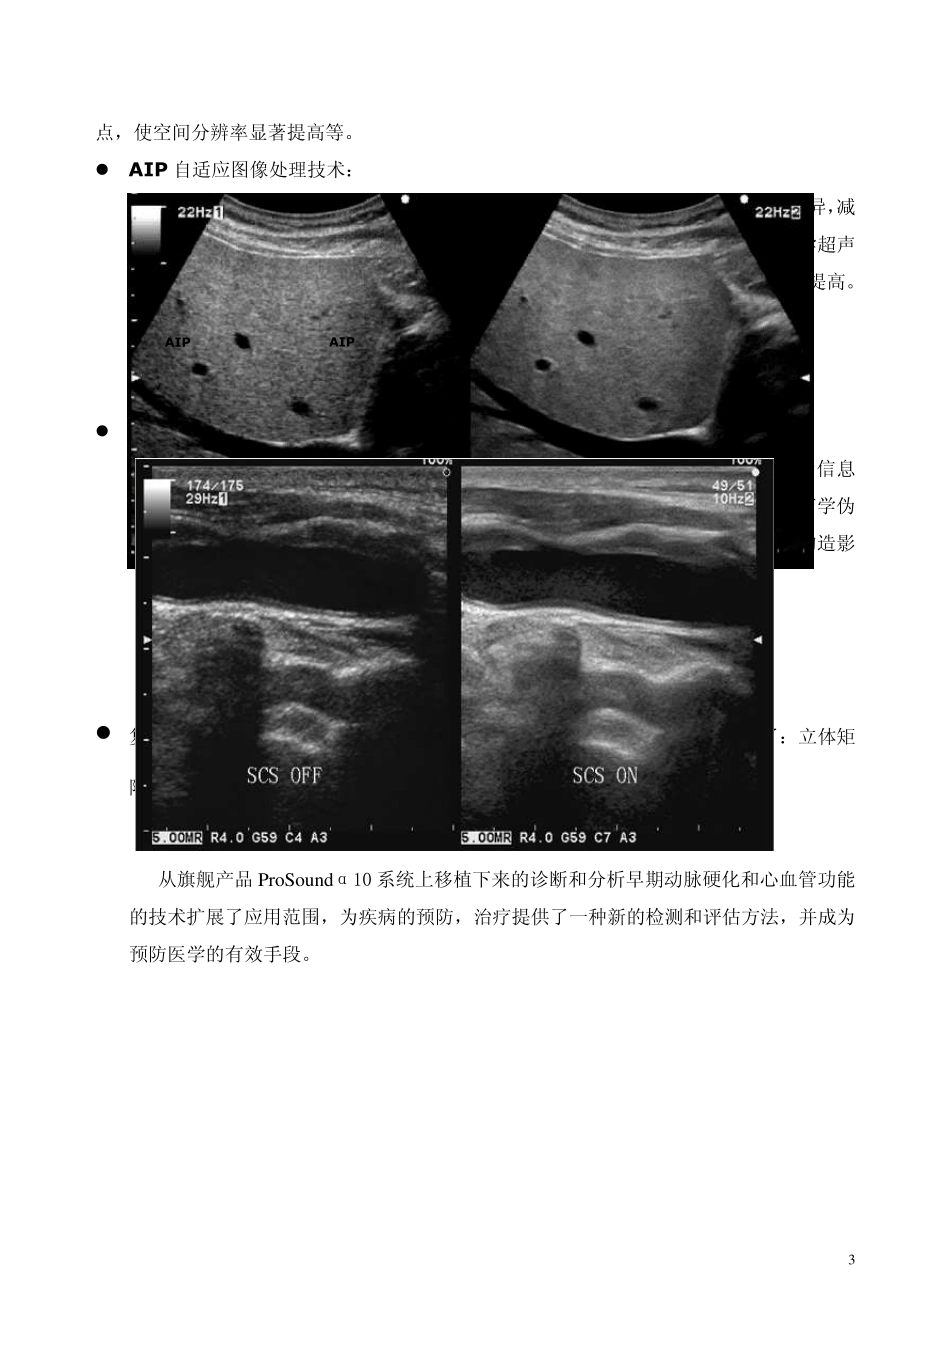

1 技 术 特 点 简 介 ALOKA THE INNOVATOR IN ULTRASOUND 2 ProSou ndα7 是 ALO KA 继推出旗舰产品 ProSou ndα10 之后的又一个得力之作。 秉承于ProSou ndα10先进的前端技术平台,ProSou ndα7获得了极高空间分辨率及时间分辨率的二维及血流图象,可以更加真实的反映微细血管的灌注情况,真实再现微细血管解剖形态。  e-Flow 技术 eFLOW 技术是基于 ALOKA 新开发的复合阵列探头,加上最新一代的复合脉冲成像技术(CPWG),从而得到精确的控制声波的发射,只产生需要的超声波,灵巧地控制多普勒信息的整个过程,完全滤除噪音干扰,得到更丰富的频移信息,从而从根本上改善血流的空间分辨率和时间分辨率,可以真实的反应微细血液循环的灌注情况,有效地控制了高灵敏度下血流的溢出情况,提供了高空间分辨率和时间分辨率的彩色血流图象,能更细微的显示末梢血流的动态情况。 临床意义:E-FLOW 能够准确显示表浅器官的肿瘤、肾实质血流和感染进程等的微细血流灌注情况;能最小限度地减少彩色的外溢,显示微细血管和低速血流;对于扫查困难病例,可以从背景噪音中提取血流信号,更大程度的显示血管的变化;完成冠状动脉-乳内动脉搭桥与各种血管外科自体、人工转流血管患者术后超声随访检查和颈动脉、腹主动脉、髂动脉、股动脉夹层动脉瘤的诊断。借助甲状旁腺、肾上腺、肾脏以及肾动脉超声检查能够很好地对原发性高血压与肾血管性高血压进行鉴别。还可用于观察器官移植、断肢再植术后的血供情况,外周血管痉挛性疾病(雷诺氏病)的诊断和鉴别诊断等。 ProSou nd α7 让检查和诊断变得更轻松!这要归功于 ProSou nd α7 优异的图像质量,以及多种可以保证或者增强诊断准确性的丰富功能。例如,通过复合脉冲波发生器,从始至终得控制超声晶片的振动和停止,实现超声晶片振动的完全控制,优化传送波形减少噪音,实现了图像空间分辨率和对比分辨率的革命性的提高;宽带谐波功能具有基频和谐波图像的优 3 点 , 使 空 间 分 辨 率 显 著 提 高 等 。  AIP 自 适 应 图 像 处 理 技 术 : 在 获 取 到 高 帧 频 的 同 时 清 晰 显 示 组 织 间 的 差 异 ,减少 斑 点 噪 音 , 完 整 细 腻 的 呈 现 灰 阶 信 息 , 医 学 超 声诊 断 的 基 础 ------二 维 图 像 质 量 得 到 了 极 大 的 提 高 。  SCS 空 ...